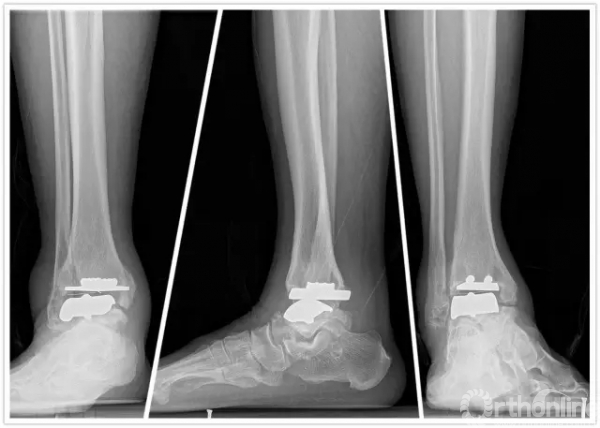

手术中首先沿原手术切口进入,保护神经血管肌腱组织,清理踝关节假体周围骨赘,取出原关节假体,将患足置于专门的定制支架中,在透视下反复调整足踝及导针位置,力求最高精确度。在导板的定位下进行胫骨远端和距骨截骨,试样假体大小,置入合适匹配的踝关节假体及垫片完成全踝关节假体的置换,然后再行距下关节融合术。历经4小时,手术过程非常顺利,术后患者恢复良好,手术取得圆满成功。